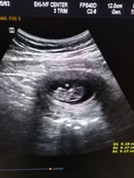

แม่ๆบ้านไหน ไปซาวด์ตอนท้องได้10 w แล้วเห็นลูกดิ้นบ้างคะ

ของเราไปซาวด์แล้วยังนอนนิ่งๆอยู่เลย #ขอบคุณสำหรับคำตอบค่ะ